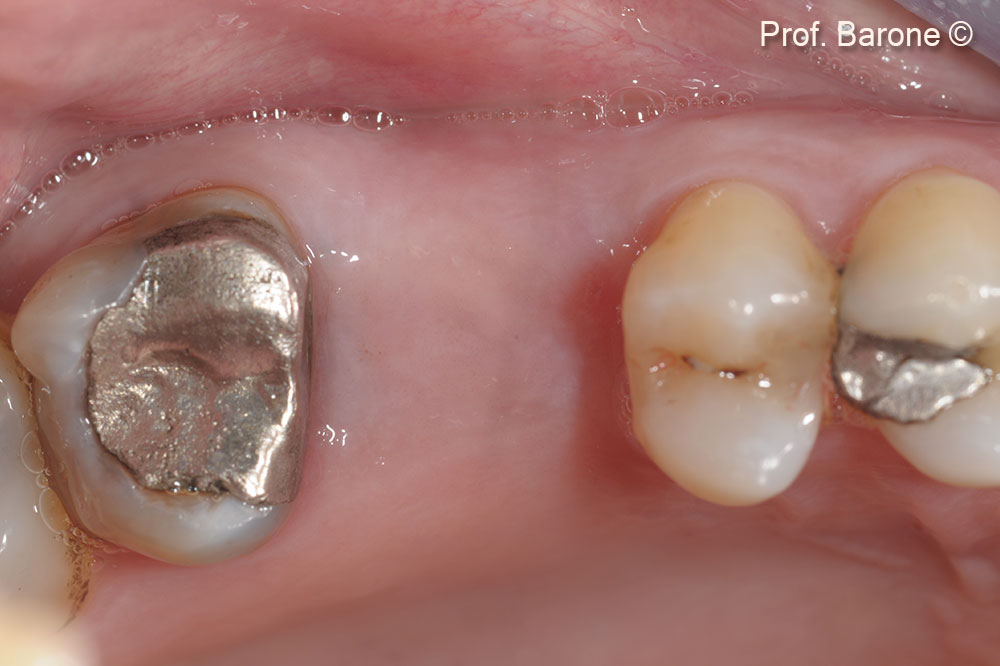

Initial situation

A male patient (53 years old) shows a fractured tooth.

Occlusal view. Tooth n 26